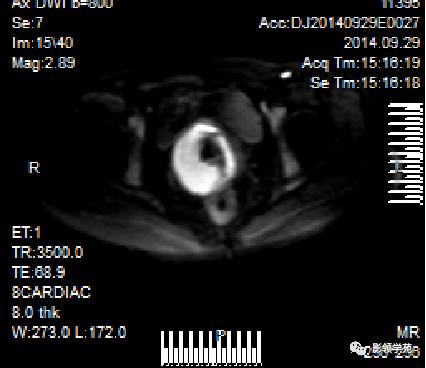

DWI:局限性高信号,癌组织ADC值<癌旁组织<小于正常宫颈组织

Ⅰ期

IIA期

IIB期